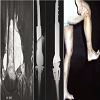

In 64 patients (31.5%) different plastic-reconstructive surgical procedures were necessary to close the soft tissue or bony defect produced by the resection of the tumour. In 17 cases simple mesh graft was sufficient (Figure 1); in 32 cases different local or free fasciocutaneous- or muscle-flaps (Figures 2 and 3) were needed. In three cases tendon transfer was necessary; vascular grafts (Figure 4) had to be performed in 8 cases. In 4 cases bony reconstructions had to be used (Figure 5) after additional resection of the involved bone or joint.

Figure 5: 56-year old man with a leiomyosarcoma involving the distal right femur: a) MRI, sagittal view; b) X-ray (a.p. and lateral view) after resection and reconstruction by a megaprosthetic replacement with joint replacement; c) functional view after 11 years showing restricted flexion of 80° possible.